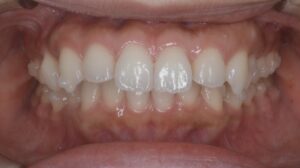

こちらは、マウスピース治療を開始して4ヶ月が経過した時点の口腔内写真です

治療前と比較すると、「本当に歯って動くんだ」と実感できる変化が出てきました。